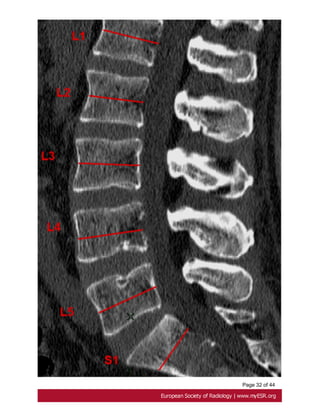

the midsagittal vertebral body diameter [28]. Fig. 19 on page 29, Fig. 20 on page 31

Page 10 of44 A less common cardiovascular manifestation of Marfan syndrome is dilatation of the main pulmonary artery. The upper values have been established at 24 mm at the pulmonary artery bifurcation and 34mm at the pulmonary artery root[23]. Fig. 15 on page 24 2- Dural ectasia Dural ectasia (DE) is one of the major criteria of Marfan syndrome in the Ghent nosology. It has a prevalence in Marfan syndrome of about 60% and its severity increases with aging[24]. It is a widening of the dural sac or spinal nerve root sleeves, usually associated with bony erosions of the posterior vertebral body, increased thinning of the cortex of the pedicles and laminae, widening of the neural foramina, or presence of a meningocele[25]. Ahn Criteria Ahn et al. described that dural ectasia is present if one major or two minor criteria are present. Major criteria: - width of the dural sac at a level below S1 greater than that above L4. Fig. 16 on page 25 - Presence of an anterior sacral meningocele. It is present when there is a herniation of the dural sac through a defect in the anterior surface of the sacrum or when the sacral meninges are herniating anteriorly into the pelvis through a widened foramen[26]. Fig. 17 on page 27 Minor criteria: -scalloping greater than 3.5 mm at the level of S1. Fig. 18 on page 27 - nerve root sleeve diameter greater than 6.5 mm at the level of L5[27]. Oosterhof criteria According to Oosterhof et al, dural sac ratio from levels L1 through S1 in adult patients have to be greater than respectively 0.64, 0.55, 0.47, 0.48, 0.48, and 0,57 in dural ectasia. A dural sac ratio is calculated for each level by dividing the sagittal dural sac diameter by the midsagittal vertebral body diameter [28]. Fig. 19 on page 29, Fig. 20 on page 31

Page 31 of44 Fig. 19: Oosterhof criteria of dural ectasia. A dural sac ratio is calculated for each level by dividing the sagittal dural sac (red arrows)diameter by the midsagittal vertebral body diameter on CT scan.

Page 33 of44 Fig. 20: Oosterhof criteria of dural ectasia. Midsagittal vertebral body diameter (red arrows) on CT scan.